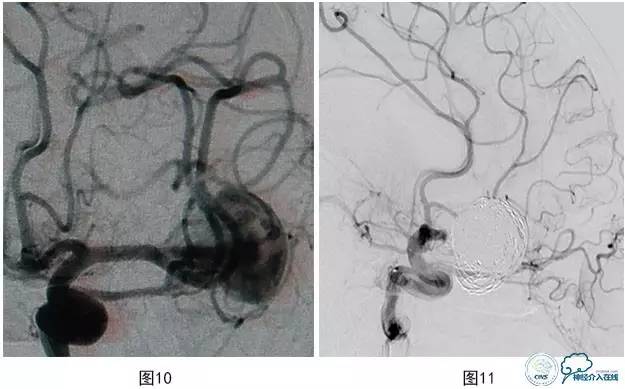

病例3:患者男,27岁。头痛2个月,左大脑中动脉M2段上干起始部靠近分叉部位巨大动脉瘤,下干起始部靠近瘤颈(图10),行支架辅助栓塞治疗,保护下干。术中载瘤动脉闭塞(图11),弹簧圈突入支架内(图12)。

将微导管超选入载瘤动脉注入替罗非班10ml(图13),导引导管内注入替罗非班5ml,血流再通(图14)。术后患者神清,对答切题,伸舌左偏,四肢可遵嘱活动,肌力5级,即刻予以阿司匹林300 mg,氯吡格雷150mg口服。术后20 min,运动性失语,反应迟钝,右侧肢体无力,右上肢肌力0级,右下肢肌力2+,左侧肢体能遵嘱活动,即刻复查颅脑数字减影血管造影(DSA)示:大脑中动脉下干支架内血栓形成,远端血流缓慢(图15)。机械碎栓,部分再通,微导管在上下干开口处2h内分次注入替罗非班共40ml,上干再通,下干分支部分再通,远端可通过软膜吻合显影(图16)。术后患者症状缓解,右侧肢体肌力4+,面瘫消失,部分运动性失语,术后替罗非班静脉微泵维持48h,术后维持收缩压120mmHg以上。术后头颅磁共振弥散加权成像(MR DWI)示左侧大脑中动脉供血区急性梗塞灶(图17)。

图10 左MCA M2段上干起始部靠近分叉部位巨大动脉瘤

图11 载瘤动脉闭塞